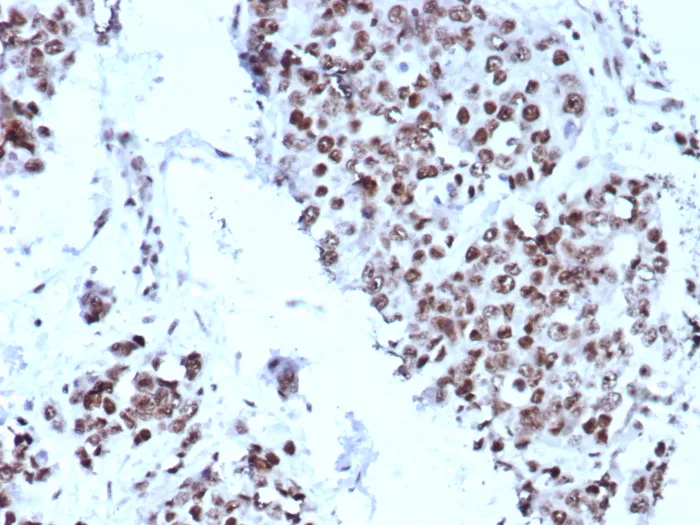

IHC analysis of formalin-fixed, paraffin-embedded human bladder. Strong nuclear staining using KIP2/8572 at 2ug/ml in PBS for 30min RT.